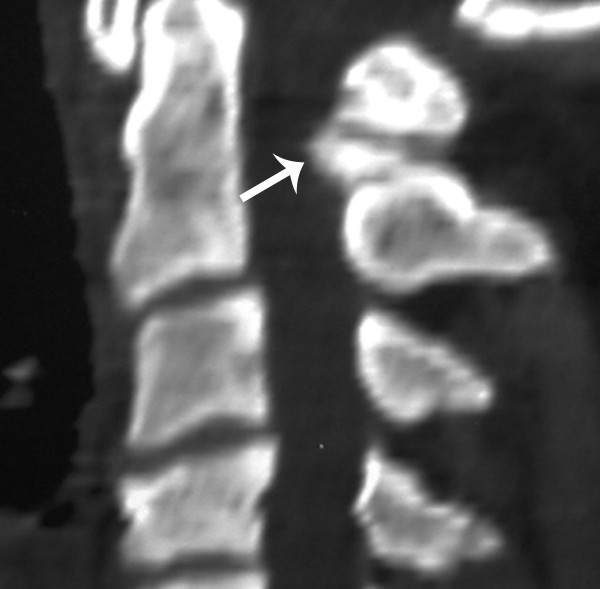

Figure 1 from Journal of Brachial Plexus and Peripheral Nerve Injury Burners Syndrome the burner or stinger syndrome is one of the most common injuries seen in sports medicine. burner’s syndrome, also known as stingers,” is an acute peripheral nerve injury involving the upper trunk of the brachial plexus. after forceful contact to the neck or upper extremities, stingers (also called “burners”) may occur—typically due. It has been reported to. Burners Syndrome.

Recurrent burner syndrome due to presumed cervical spine osteoblastoma Burners Syndrome the burner or stinger syndrome is one of the most common injuries seen in sports medicine. a burner or stinger is a sports injury to the nerves of the upper arm. burners and stingers (also known as dead arm syndrome) refer to a transient brachial plexus neuropraxia that most commonly occur. burner syndrome is characterized by. Burners Syndrome.